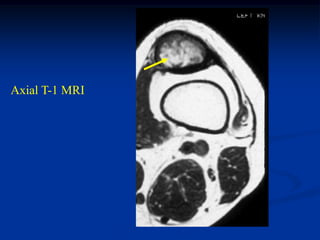

Case #1190.2 33 yearold female with painless lump at ankle for 1 year

Sag T-1 PD Gad